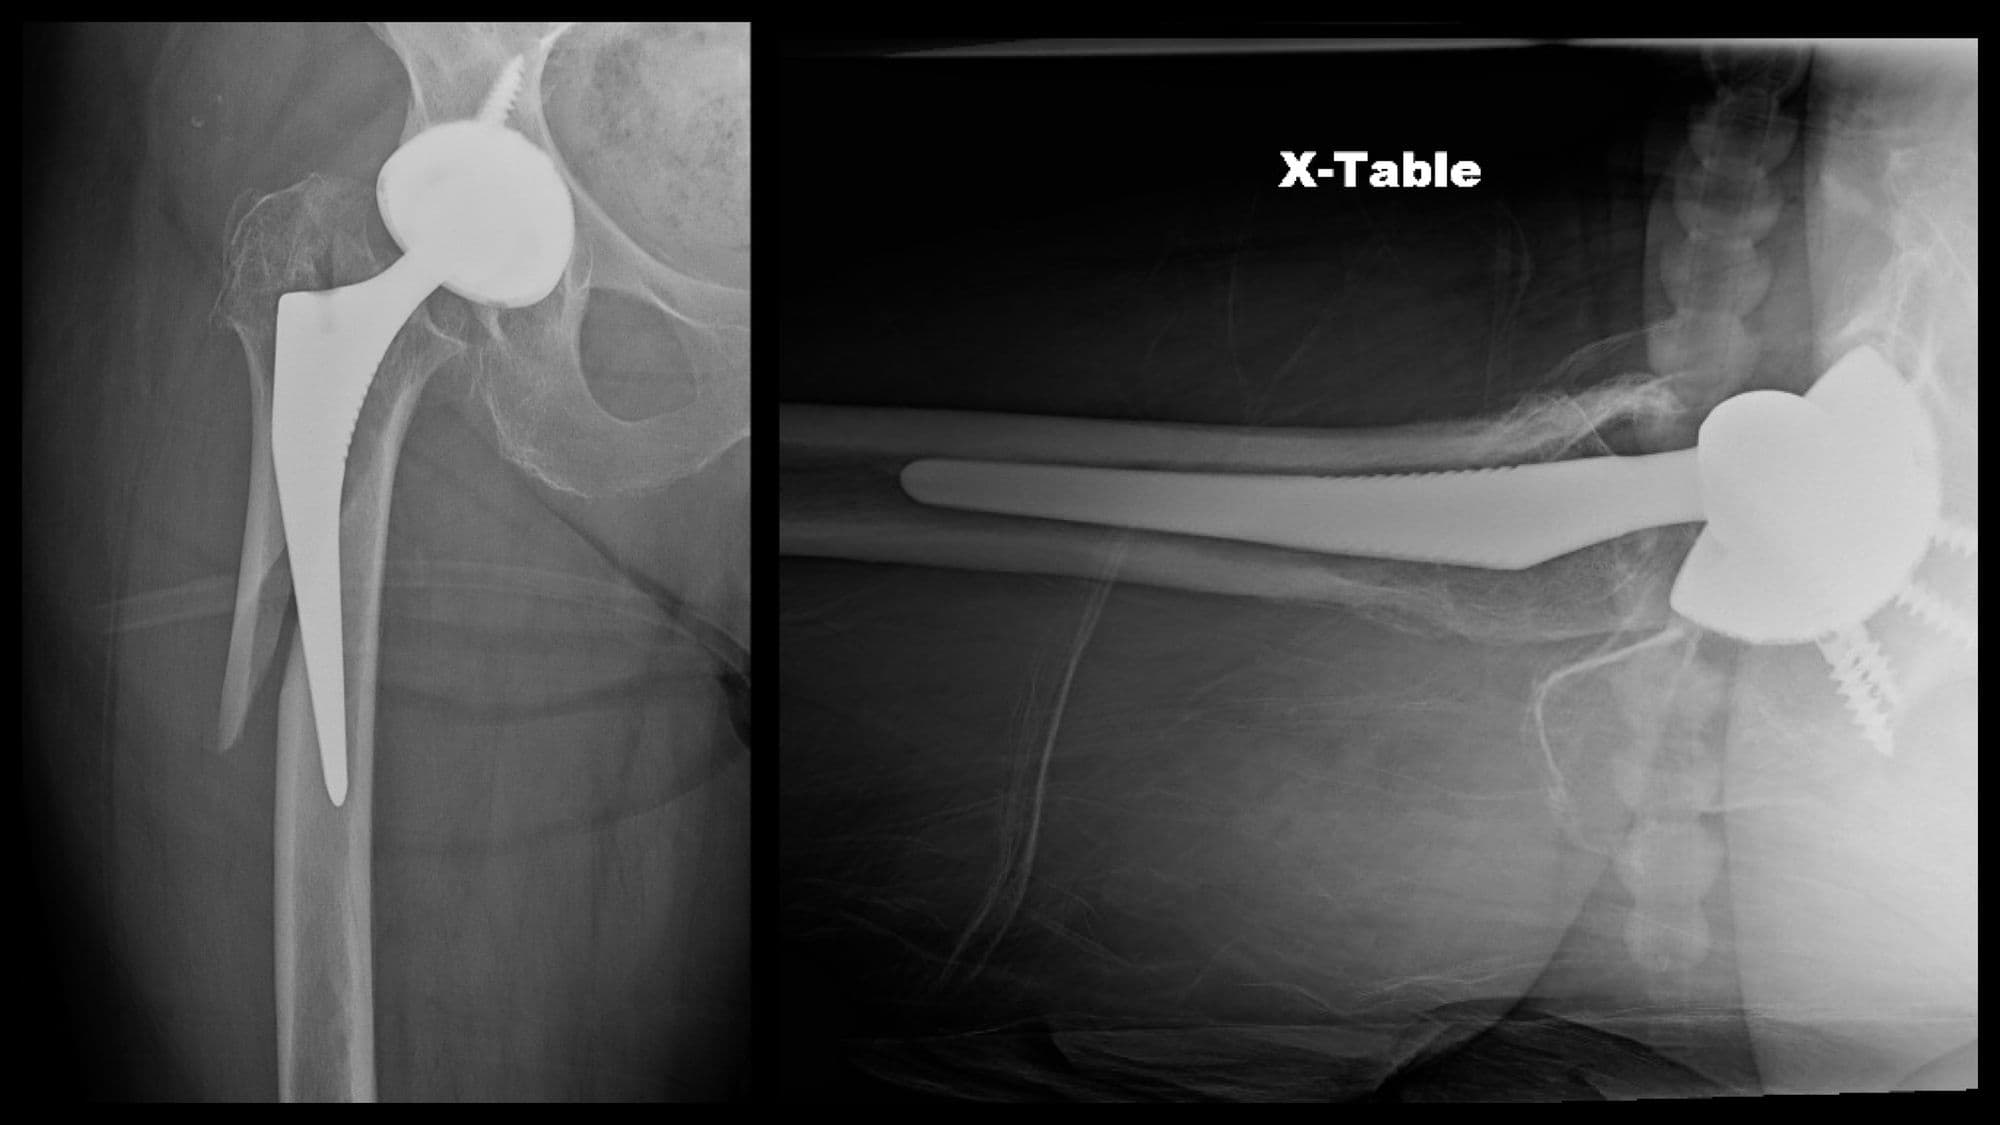

Intertrochanteric Fracture Short Nail